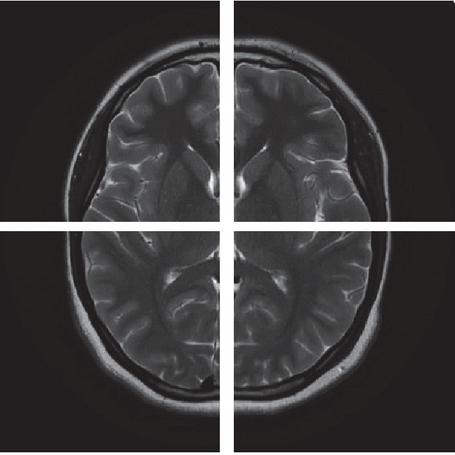

images

Figure 1 Demonstrates how the original image was divided into four parts.

3.1 Compute Chaos Parameter Values

The proposed medical image encryption algorithm uses randomly chosen pixel values from the original image to generate control parameters for both the WAM and Uruk systems. This process adds a layer of security because the encryption keys change each time the algorithm is executed. Figure 1 depicts the process of dividing the input image into four equal parts prior to the random selection of pixels from each section. The calculation of control parameters includes the subsequent steps: